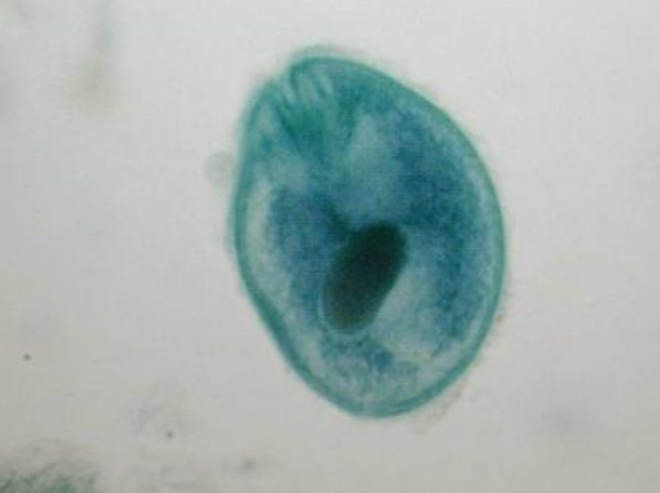

Balantidium coli cyst